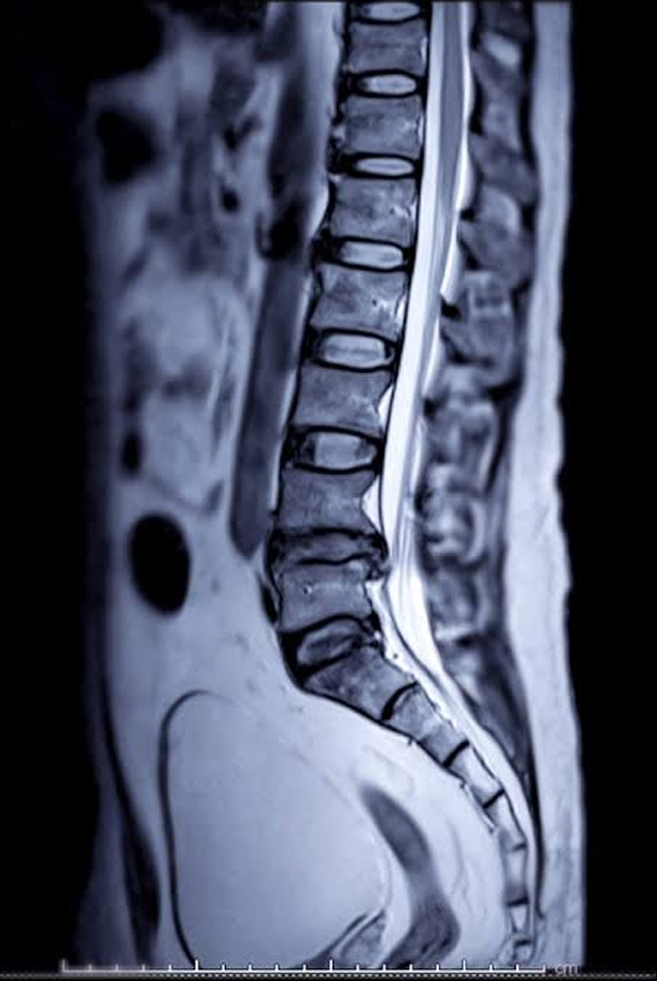

When you consult us we do thorough examination and clinical diagnosis done. We recommend surgical or non surgical treatment only after thorough study of your x-ray and MRI.